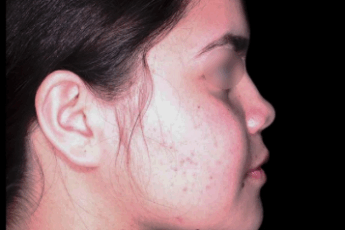

El liquen plano oral es una condición inflamatoria crónica que causa manchas blancas o rojas en la boca.